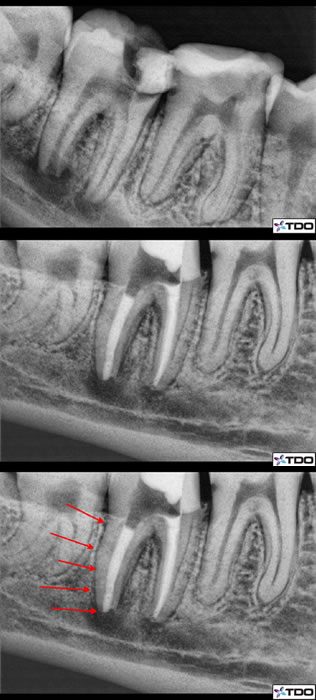

Figure 1

Figure 2: Pre-op radiograph with an apical lesion and an “open” apex. A very important canine tooth and part of a bridge. Figure 3: The immediate post-op following 2.5 months of CaOH treatment. Figure 4: Red arrows indicating the MTA location with gutta percha packed on top of the MTA. There is already a noticable healing response occuring apically as well.

Figure 7: Here is a case of Dr Monroe in which he had to perform RCT on an immature apex. The distal root is far too open to place gutta percha and thus he filled the entire distal root with MTA (red arrows).